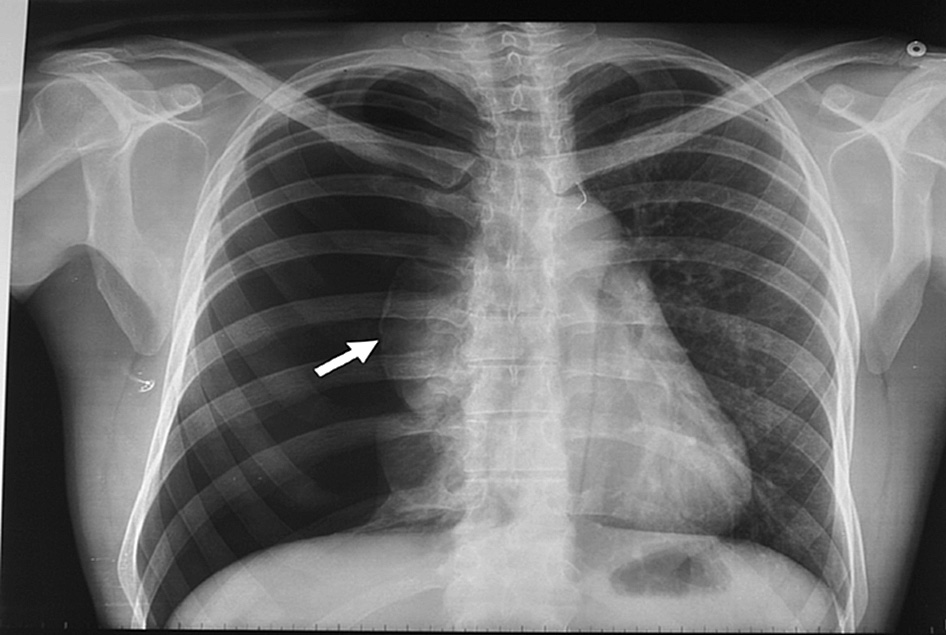

En un ensayo clínico que comparó la intervención inicial vs manejo conservador se encontró resolución del neumotórax a las 8 semanas en 98,5% vs 94,1% de los pacientes, respectivamente. New England Journal of Medicine, 30 de enero de 2020